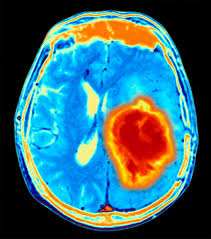

The signs may vary according to the type, size, and location of the tumor or the age of the child. Research indicates that prolonged, severe headaches that seem to worsen early in the morning or during physical activity could be a potential sign of brain cancer. They most commonly develop in children ages 5 to 8. The signs and symptoms of brain tumors vary widely, but include: This is the front of the brain.

Alan cohen, m.d., director of pediatric neurosurgery at johns hopkins children's center, shares the most common signs and symptoms that could point to a potential brain tumor. Some of the more common symptoms of a brain tumor in children include: Brain cancer is the most common form of cancer death in people under 40 and for such a serious disease, it hasn't received as much attention as other cancers. Symptoms from pediatric brain tumors vary widely, depending upon the tumor's location and size. Join david arons, ceo of the national brain tumor society, and the entire brain tumor community for an update on the progress we have made in the fight to conquer and cure brain tumors, and the critical work that lies ahead in 2021. A brain tumor can cause symptoms by directly pressing on the surrounding parts of the brain that control certain body functions, or by causing a buildup of spinal fluid and pressure throughout the brain (a condition known as hydrocephalus). A brain tumor is an abnormal growth of tissue in the brain. Sometimes, children with a brain stem glioma do not have any of these changes. Brain tumors are the second most common form of childhood cancer. Signs and symptoms may be caused by childhood brain stem gliomas or by other conditions. The cns also includes the spinal cord. Signs or symptoms vary depending on a child's age and the location of the tumor, but may include: The most common symptoms include:

Sometimes, children with a brain stem glioma do not have any of these changes. Headaches that get worse over time are a common symptom of brain tumors. Take up space inside the skull when they grow cause specific symptoms due to the position of the tumour in the brain In general, brain tumors in children are very rare. Headaches, which may become more frequent and more severe feeling of increased pressure in the head unexplained nausea or vomiting Still, cancer is the second leading cause of death in children younger than 15 years old, after accidents. Symptoms may occur when a tumor presses on a nerve or damages certain parts of the brain. The cns also includes the spinal cord. Brain tumor signs and symptoms morning headache or headache that goes away after vomiting. Research indicates that prolonged, severe headaches that seem to worsen early in the morning or during physical activity could be a potential sign of brain cancer. Brain tumors are the second most common form of childhood cancer. Or, the cause of a symptom may be a different medical condition that is not a brain stem glioma. Infants and young children whose fontanels haven't yet closed may have virtually no detectable signs or symptoms of a brain tumor except for an increasing head circumference, which occurs because the skull expands as the tumor grows.

The symptoms of a pediatric brain tumor vary according to the size, type and location of the tumor. The main parts of the brain are: Check with your child's doctor if your child has any of the following: The cns also includes the spinal cord. The most common forms of brain tumors are: They may also occur when the brain swells or there is fluid buildup in the skull. Keep in mind, headaches are not usually early warning signs, but can occur once a tumor has reached a considerable size. Infants and young children whose fontanels haven't yet closed may have virtually no detectable signs or symptoms of a brain tumor except for an increasing head circumference, which occurs because the skull expands as the tumor grows. In children, tumors usually start in a part of the brain that controls movement and coordination. The brain is part of the central nervous system (cns). Brain cancer is an overgrowth of cells in your brain that forms masses called tumors. Take up space inside the skull when they grow cause specific symptoms due to the position of the tumour in the brain But not all brain tumors cause headaches, and most headaches are not caused by tumors.